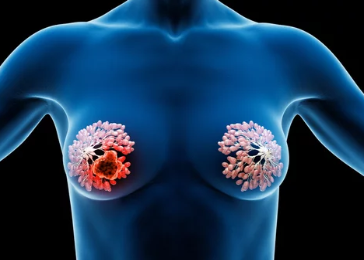

갑상선 유두암은 갑상선암 중 가장 흔한 유형으로, 비교적 예후가 좋은 암으로 알려져 있습니다. 특히 조기에 발견하면 높은 완치율을 보이며, 크기에 따라 치료 결과가 달라질 수 있습니다. 이번 글에서는 갑상선 유두암의 크기별 완치율과 관련 정보를 자세히 알아보겠습니다.

1. 갑상선 유두암이란? – 기본 개념과 특징

갑상선 유두암은 갑상선 세포에서 발생하는 악성 종양으로, 다음과 같은 특징을 가집니다.

- 가장 흔한 유형: 전체 갑상선암의 약 85%를 차지하는 가장 흔한 형태의 갑상선암입니다.

- 천천히 진행: 암의 진행 속도가 느리며, 조기에 발견하면 치료가 쉽습니다.

- 다른 장기로의 전이 가능성: 드물지만 림프절이나 폐, 뼈 등으로 전이될 가능성도 있습니다.